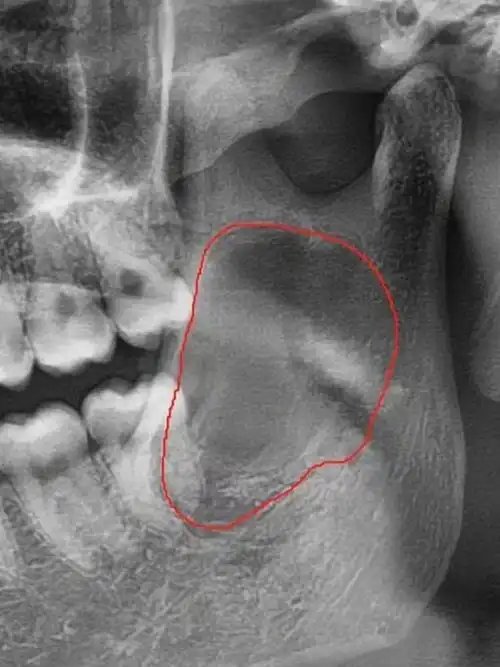

12岁小朋友-下颌骨囊肿.12岁小朋友牙齿检查,发现右侧下颌 - 抖音

补牙之后想要拔智齿,拍完ct后,发现红圈圈的地方疑似囊肿,建议去公立

ct看看,赶紧去,赶紧去,赶紧去,不要想我一样没感觉觉得没事,最后囊肿